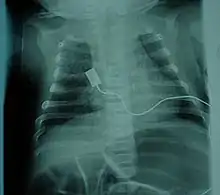

| Location of neurons affected by spinal muscular atrophy in the spinal cord | |